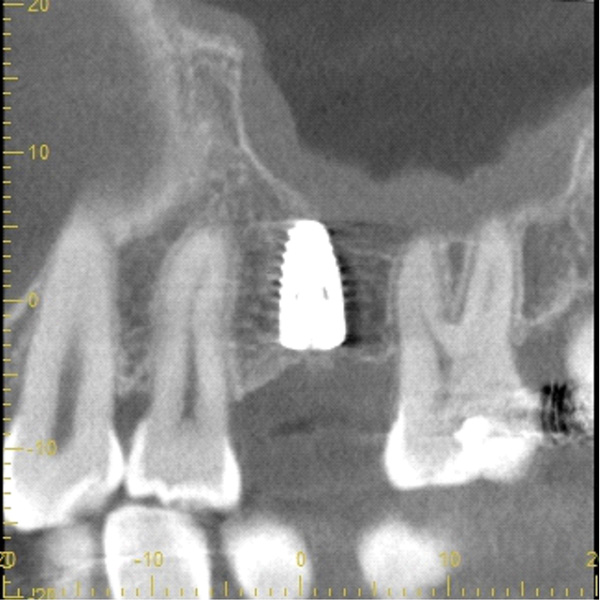

| 主訴 | 右下の歯がないのでインプラントをして欲しい |

| 治療期間 | 約6ヶ月 |

| 費用 | 600,000円 |

| 治療内容 | インプラント、骨造成、結合組織移植、セラミック修復 |

| 治療に伴うリスク | インプラント周囲炎 セラミックの破折、脱離 |